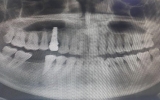

[나이스데이] 최근 '수면 임플란트'를 앞세워 홍보하는 치과가 늘어난 가운데 치과의사단체가 용어 오인이 부른 안전 불감증을 경고했다. 치과 임플란트에서 사용하는 '의식하진정법'은 위 또는 대장내시경 검사를 받을 때 선택할 수 있는 수면 마취와는 다르다는 것이 대한치과의사협회의 설명이다. '의힉하진정법'은 자발적 호흡이 가능한 정도로, 의학적 의미의 수면과는 엄밀히 구분된다는 것이다. 29일 의사협회 의료광고심의위원회에 따르면 수 년 전 이미 '수면 임플란트'라는 표현이 환자에게 시술의 위험성을 간과하게 하고 치료 효과를 오인…